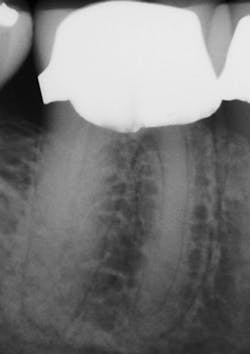

Figure 1: Radiograph of extracted tooth to demonstrate preoperative canals.

After preparing straight-line access to the canal orifice (figure 1), explore the canal using small-sized instruments. I typically use a size 08 SafeSider by hand with the help of an apex locator to determine working length. I then use the SafeSiders in sizes 10, 15, and 20 to verify patency and confirm a smooth, reproducible glide path (figure 2). I always irrigate and enlarge the glide path to a minimum 20/02 preparation.